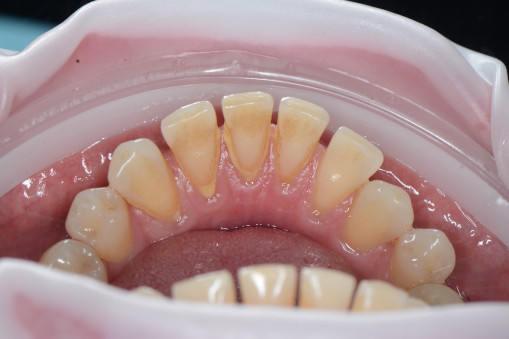

А прежде, чем вы посмотрите фотографии «до» и «после» лечения слизистой оболочки полости рта, проведенных в нашей клинике, хочу поблагодарить большое количество наших пациентов, которые поверили, прониклись нашей концепцией, и мы вместе, именно вместе победили болезни десны, гингивит и пародонтит!

До/после лечения